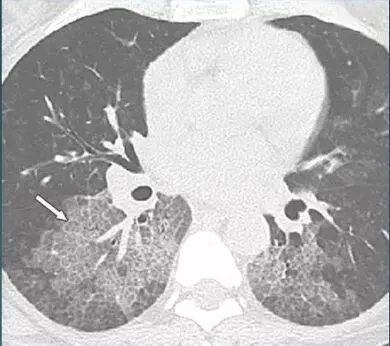

上图是一例PAP的病人,肺内:小叶间隔及小叶内间隔增厚,不是蜂窝征。